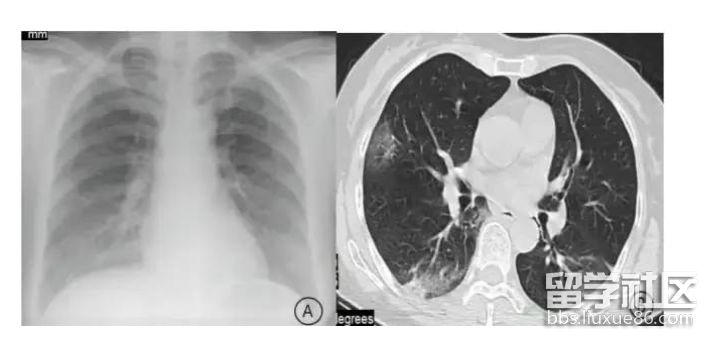

甲流将导致重度肺炎

四类人群易出现“白肺”问题

此次肆虐的甲流病毒,曾在2009年引发了26%的重症病死率,其中孕妇死亡率达40%!

在呼吸科医生看来,流感致死的一个重要原因就是,它侵蚀肺部导致重度肺炎从而让患者缺氧而死。所以,这也是此次甲流患者中出现“白肺”的原因。

目前已有的病例统计中,老年人、儿童、孕妇和有基础疾病的人群均是“白肺”的高发人群。